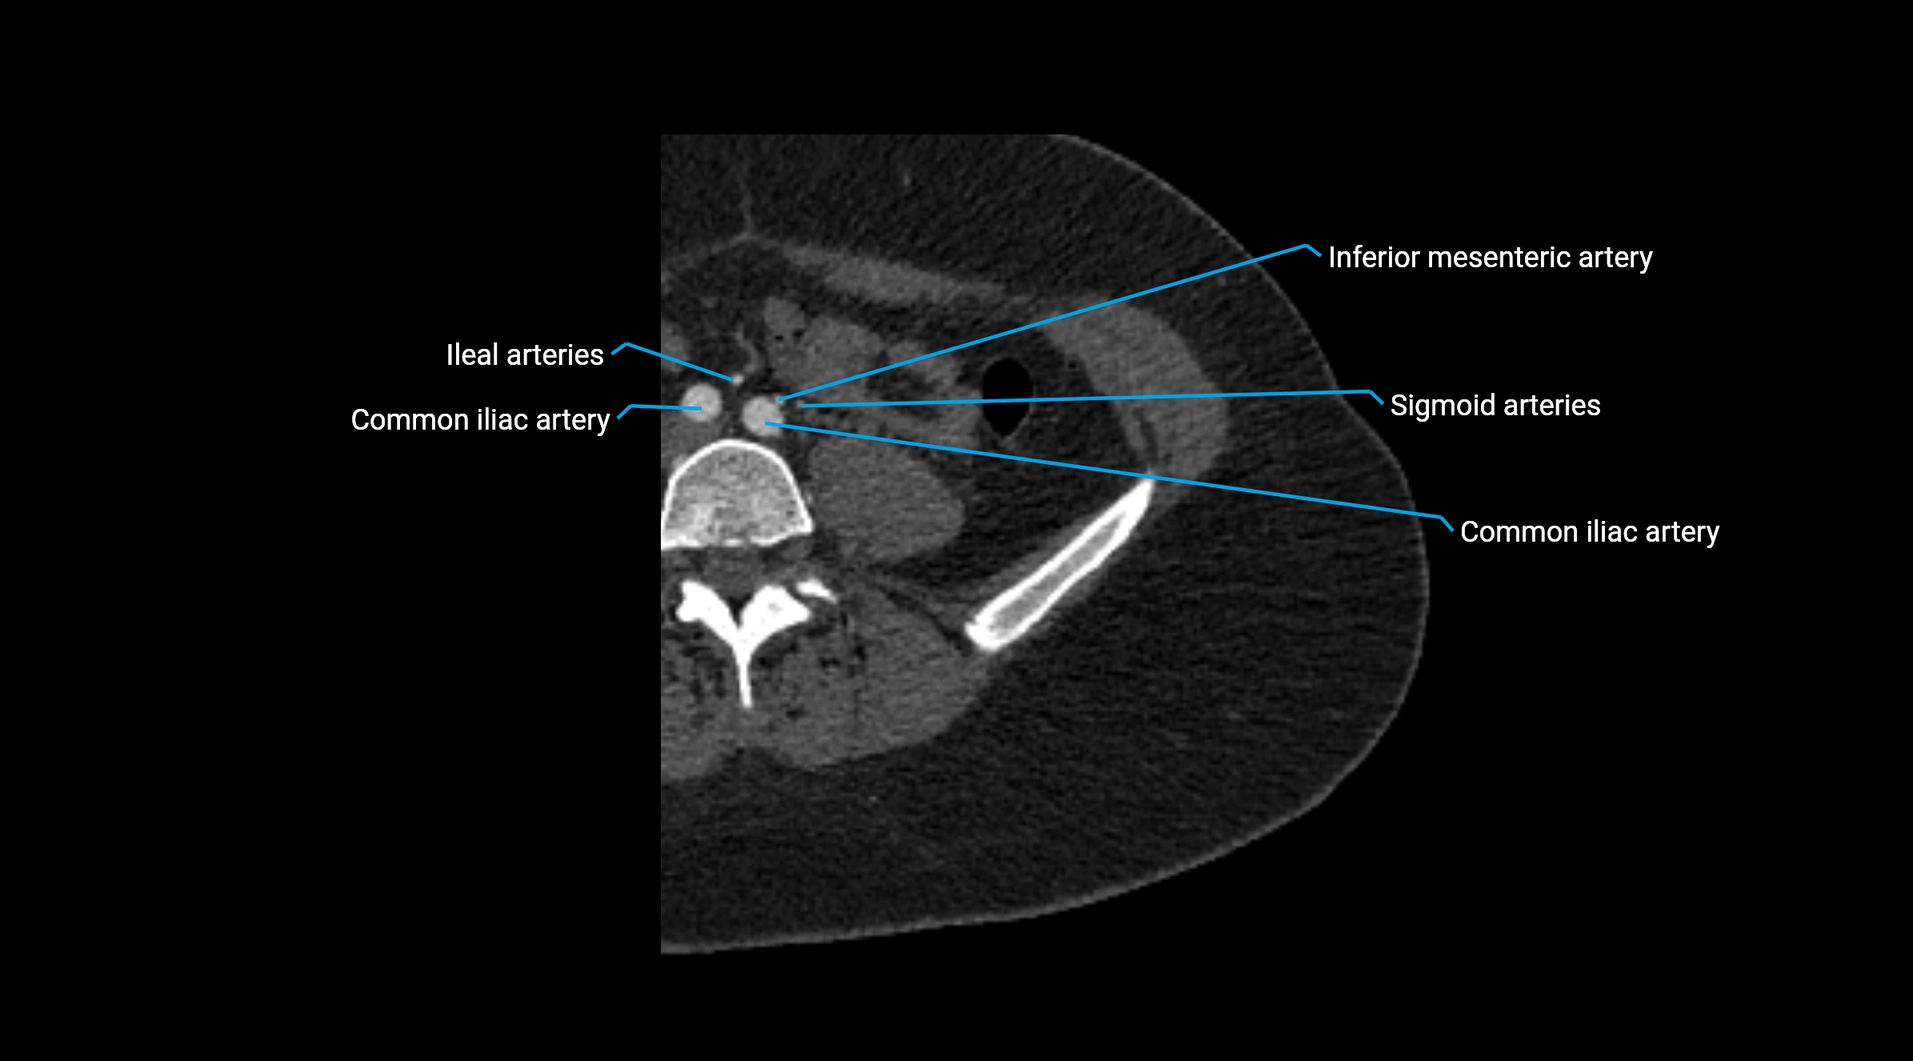

CT images

image